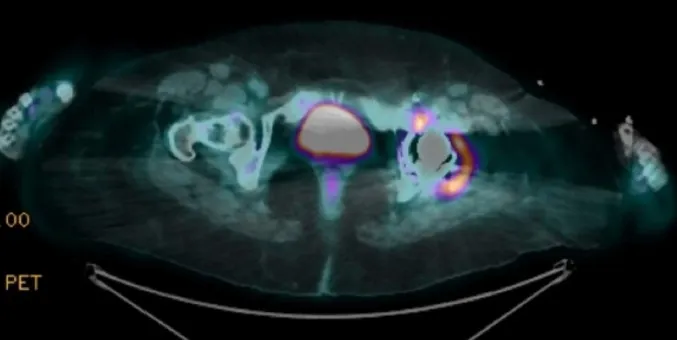

Hipercalcemia em DRC no pós-artroplastia: e se o vilão não for o PTH? Pistas discretas — 1,25(OH)₂D↑, ECA↑ e PET “quente” na prótese — apontam para ASIA por cimento ósseo. Acompanhe o raciocínio que faz o diagnóstico emergir e muda a conduta.